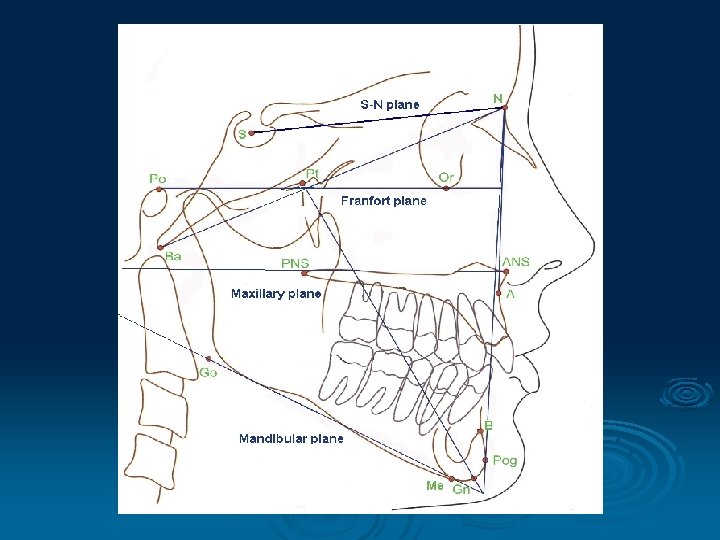

Cephalometric point, plane, line and angles used in dentistry S (Sella) midpoint of sella turcica N (Nasion) most anterior point on fronto-nasal suture Or (Orbitale) most inferior anterior point on margin of orbit Po (Porion) upper most point on bony external auditory meatus ANS (Anterior Nasal Spine) PNS (Posterior Nasal Spine)

Go (Gonion) most posterior inferior point on angle of mandible Me (Menton) lower most point on the mandibular symphysis A (A point) position of deepest concavity on anterior profile of maxilla B (B point) position of deepest concavity on anterior profile of mandibular symphysis

Frankfort Plane: Po - Or Equivalent to the true horizontal when patient is standing upright Maxillary Plane: PNS - ANS Gives inclination of maxilla relative to other lines/planes Mandibular Plane: Go - Me Gives inclination of mandible relative to other lines/planes

Important lines: S - N line N - A line N - B line Important angles: SNA SNB ANB Indicates position of maxilla / mandible to each other and to the cranial base